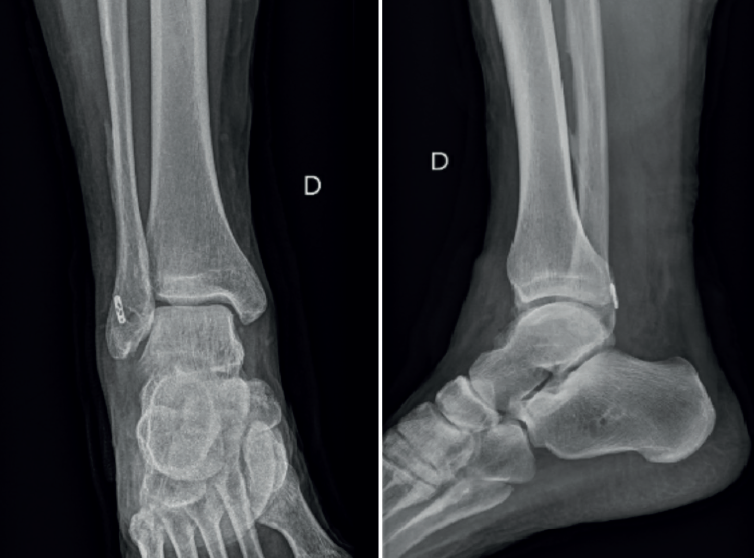

Un año y medio después de la lesión inicial, se realizó una segunda cirugía artroscópica de tobillo. El procedimiento reveló sinovitis anterior de la articulación tibiotalar, que fue desbridada con un sinoviotomo. El CFL estaba intacto, mientras que se observó una rotura parcial menor del ATFL, que se consideró clínicamente sin relevancia. En segundo lugar, se realizó una tenoscopia de la vaina de los tendones peroneos, revelando una rotura de la vaina y el tendón peroneus brevis con integridad del retináculo, visualizándose la fijación proximal del injerto en la fíbula que estaba en contacto con el tendón peroneus brevis, el cual estaba parcialmente desgarrado (Figura 3).

Figura 3. Tenoscopia de la vaina peronea en el tobillo derecho, donde se observa el dispositivo de fijación proximal dentro de ella, contactando con el tendón del peroneo corto durante las maniobras dinámicas.